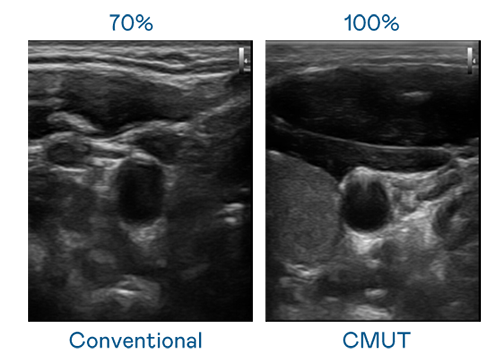

CMUT 技术是一种用电容式微机电元件来产生超音波讯号的技术。与传统 PZT 压电式技术相比,CMUT 频宽增加 30%,更宽频的超音波讯号让影像解析度大幅提升,是实现高影像品质医疗超音波扫描、促进精准医疗发展的关键技术。

超音波影像的解析度高低,首先取决于探头能发出的讯号频宽。Z6·尊龙时凯 CMUT 可提供高清晰的超音波讯号,提供高频宽、高灵敏度、影像纹理细节更高的超音波影像,协助医护人员缩短影像判读时间及利用精准的医疗影像进行诊断。